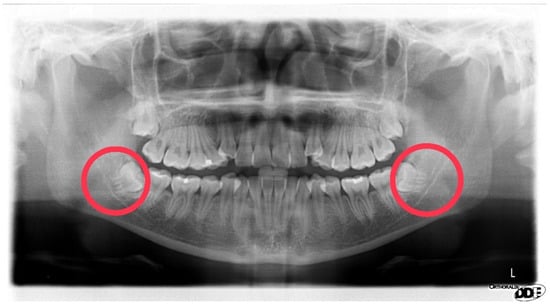

In clinical practice, dentists often rely on their experience to visually assess the contact relationship between impacted teeth and the IAN based on DPR images. However, there remains a chance of misjudgment by dentists. Therefore, through the auxiliary system developed in this study, clinicians can now utilize assistance in diagnosing the true contact relationship between impacted teeth and the IAN based on DPR images. If contact between the inferior alveolar nerve and the mandibular third molar is suspected on DPR images, CT images can be used to further identify the inferior alveolar nerve, which provides dentists with more convenient and efficient consultations. Figure 15 explores the relationships between eight sets of mandibular third molars and the inferior alveolar nerve. By utilizing the image localization segmentation algorithm developed in this study along with CNN training models for pathological assessment, it is evident that the judgment results are highly accurate.

Figure 15. Validation in the relationship between the impacted tooth and the IAN.